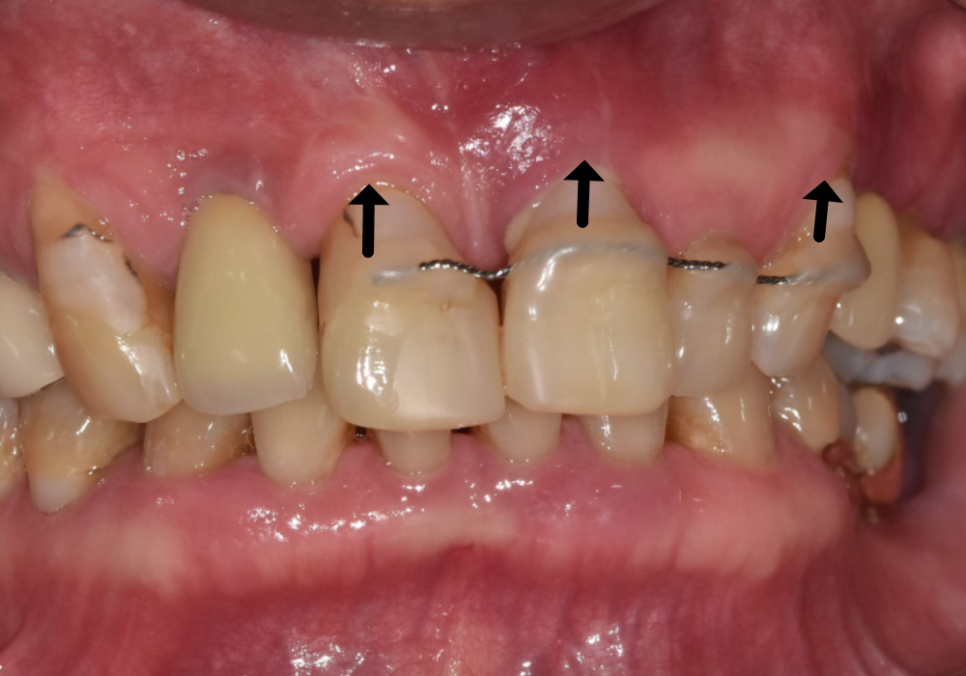

이번 환자분은 앞니가 많이 흔들렸습니다.

잇몸도 계속 부었다 가라앉았다를

반복하셨다고 합니다.

앞니가 너무 흔들리다 보니,

흔들리는 앞니 3개를

왼쪽 송곳니에 철사로

연결(스플린트) 해서 생활하고 계셨어요.

스플린트는 쉽게 말하자면,

흔들리는 치아들을

튼튼한 옆 치아랑 한 덩어리로 묶어서

힘을 나눠 받게 하는 방법입니다.

250106 스플린트로 묶인 치아

잠깐은 버틸 수 있지만,

근본 문제가 해결된 건 아니죠.

즉, 이 환자분은

"조금 흔들리는 수준"이 아니라

더 이상 미루기 어려운 수준의

흔들림이 있었다는 뜻입니다.